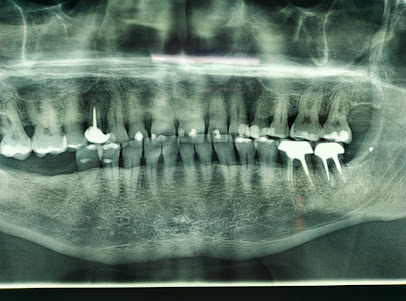

dente 37 comprometido imagem JCW